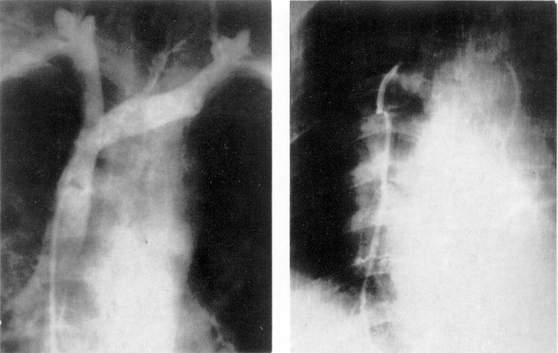

Бронхография легких может быть выполнена под наркозом. Особенность ее проведения заключается в том, что больной лежит на спине, осуществляется искусственная вентиляция легких в условиях миорелаксации. Контрастное вещество вводят через интубационную трубку и в период кратковременного апноэ выполняют рентгенограммы обоих легких в прямой и косых проекциях (рис. 5).

Рис. 5. Поднаркозная бронхография у ребенка. Косая проекция. Норма.